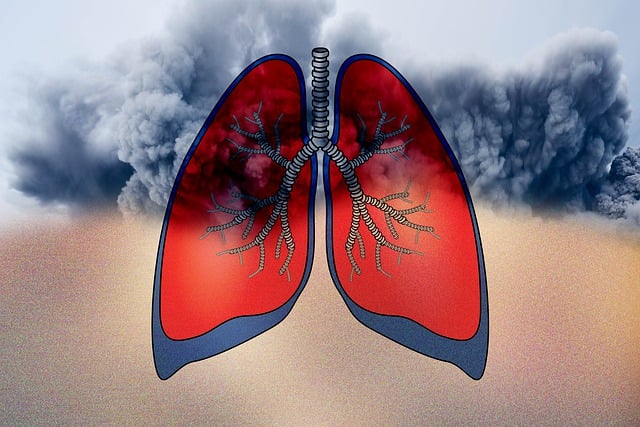

초미세먼지(PM2.5)는 머리카락 굵기의 1/30 크기로 눈에 보이지 않을 정도로 작은 먼지 입자입니다.

호흡기를 통해 폐 깊숙이 침투하며, 혈액까지 흡수될 수 있어 건강에 심각한 영향을 미칠 수 있는 주요 원인으로 꼽힙니다.

👩⚕️ 호흡기 질환 유발

- 증상: 기침, 가래, 목 통증 증가

- 질환: 천식, 기관지염, 폐렴 등 악화